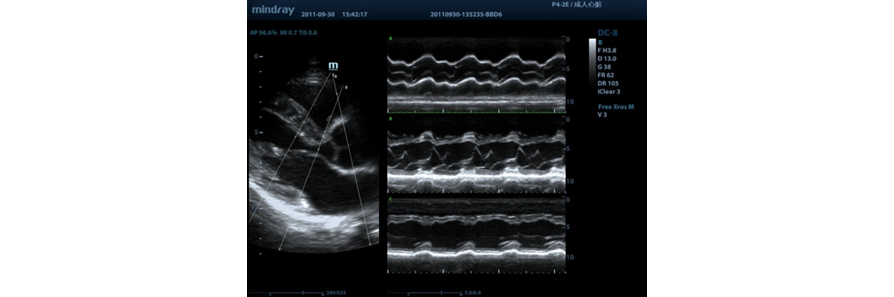

Free Xros M?

Voor nauwkeurige anatomische observatie door het vrij plaatsen van monsterlijnen onder elke hoek. Voor betere beelden door gelijktijdige weergave van tot monsterlijnen.